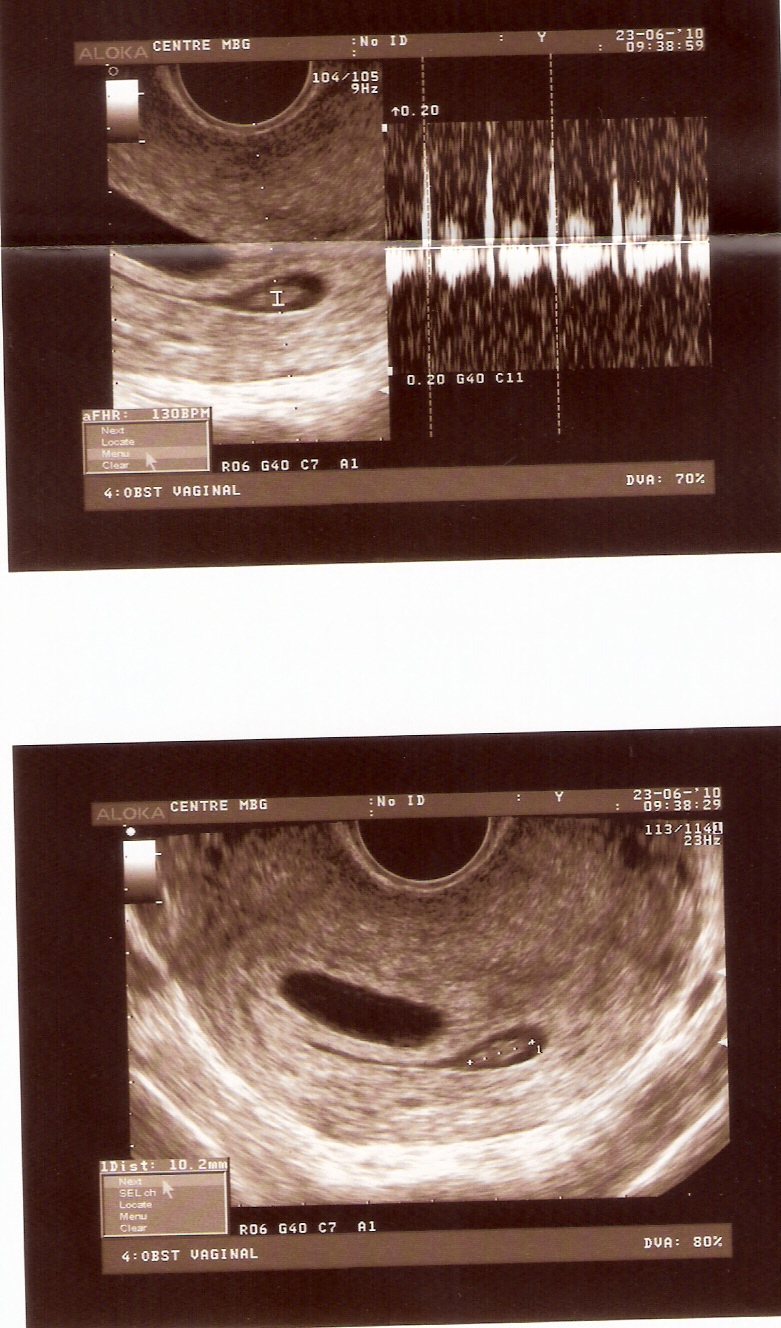

IN BTWIN Las ecografias de mis hermanos/ My brothers ultrasounds Do Twins Show Up On First Ultrasound healthcare providers can detect twins early using ultrasound. the international society of ultrasound in obstetrics and gynecology (isuog) recommends that twin fetuses. twins can show up on an ultrasound as early as 5 weeks into the pregnancy, but it’s also possible for an ultrasound to miss them. A twin pregnancy raises the risk of complications for the. Do Twins Show Up On First Ultrasound.

IN BTWIN Las ecografias de mis hermanos/ My brothers ultrasounds Do Twins Show Up On First Ultrasound This type of ultrasound allows. the international society of ultrasound in obstetrics and gynecology (isuog) recommends that twin fetuses. During this time, the ultrasound technician will look for two gestational sacs in the uterus, which can indicate twins. when can twins be seen on ultrasound? when it comes down to detecting twins in an ultrasound, it depends. Do Twins Show Up On First Ultrasound.